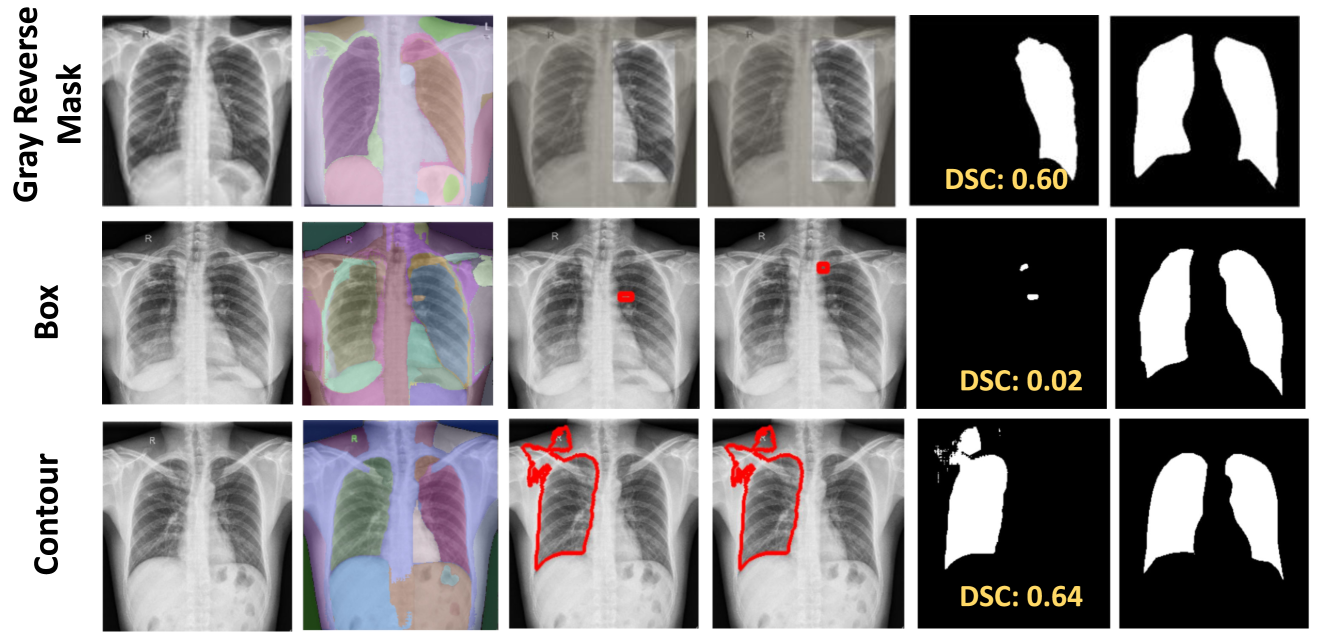

Recent research indicates that CLIP performance can be enhanced through the utilization of visual prompting [31, 24, 32, 26]. Visual prompting (VPT) involves the addition of markers like colorful boxes or circles directly onto an image, aiding in highlighting specific targets in image-language tasks. This technique directs the attention of Vision-Language Models towards desired targets while maintaining the global context. Inspired by this, we also used visual prompting to further evaluate using a separate set of prompts for the lungs. We evaluated three different visual prompts: red bounding box, gray reverse blur, and contour. In our case, we add visual markers on the original image around SAM-generated masks, and pass this set of images to CLIP, as discussed in supplementary Sec. 7. However, for medical datasets, visual prompting did not perform well. In contrast to such techniques, our method, which involves employing a set of crops of the image according to SAM-generated masks, even while utilizing separate prompts for the left and right lung, still achieves a superior DSC of 0.65 as compared to other prompts as shown in Tab. 3.

Prompt Box Reverse blur Contour Crops (ours)

DSC 0.49 0.60 0.61 0.65

7 Visual prompting

In this section, we provide details of different visual prompts around all the SAM’s generated masks to improve lung segmentation. We applied three distinct visual prompts (VPTs) to all SAM-generated masks on the input image: a red bounding box marker, contour delineation, and a reverse gray box highlighting the masked area while blurring the rest of the image [31]. However, VPTs do not improve performance for medical imaging datasets as depicted in  Fig. 11. While in certain instances a single ROI is predicted correctly, the overall recognition is inconsistent across the dataset, indicating scalability issues.

Refer to caption

Figure 11: VPT results on X-ray labels and masks  [19] dataset: Although SAM successfully generates masks for both lungs, VPTs do not facilitate CLIP in accurately retrieving ROIs.